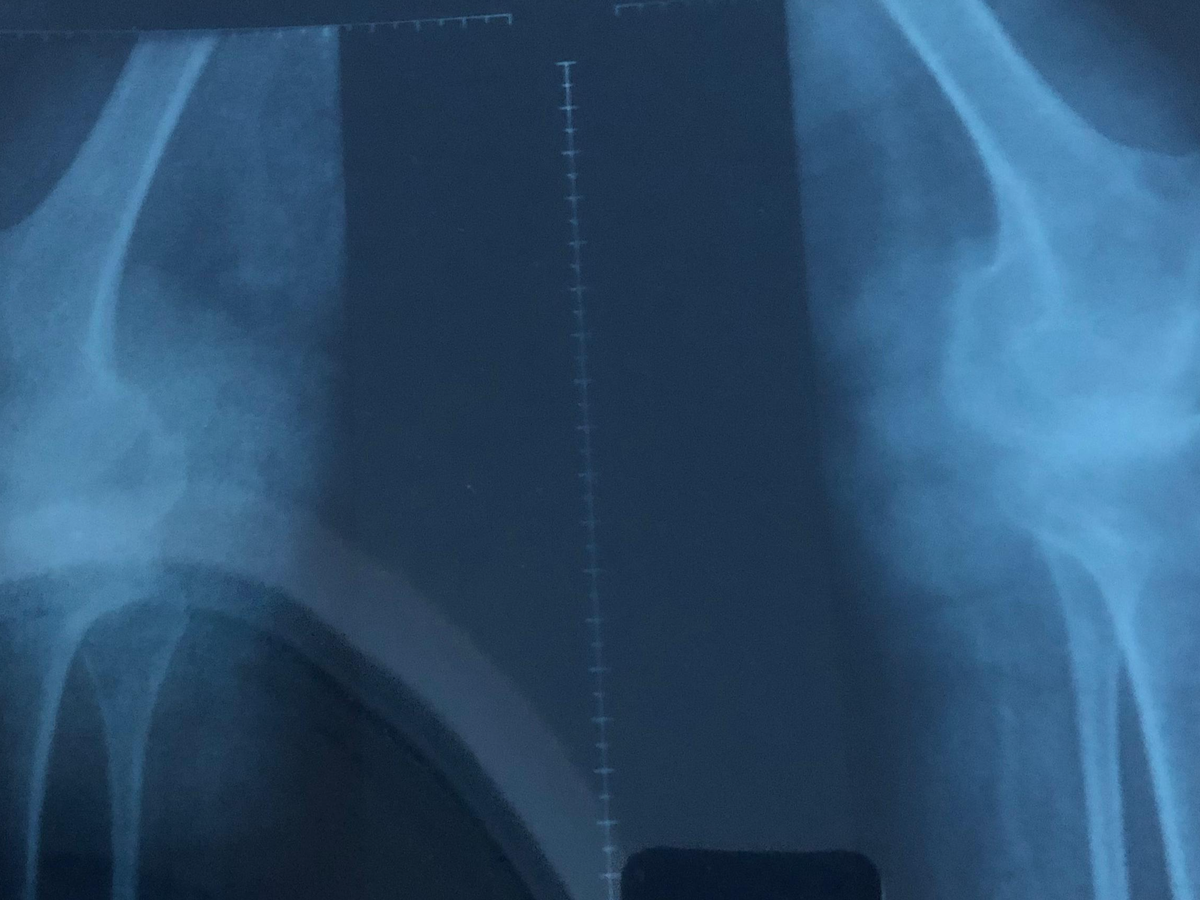

Soy Venezolana y nací con artritis Reumatoidea Juvenil, actualmente tengo 33 años, mi enfermedad a evolucionado a artritis Reumatoidea gotosa y en muchas partes ya tengo artrosis.

Hoy necesito prótesis en ambas caderas y ambas rodillas, las cuales son de reemplazo total.

Me fui de Venezuela a Argentina porque me dijeron que acá podrían ayudarme y aunque pueden operarme, no me pueden dar las prótesis adecuadas para mí condición de salud y edad. Las que me recomiendan son las de mejor calidad, durabilidad y por ende las más costosas!!. (Bioimpianti italiana ip magnam o Artrotek maxx americana. Para reemplazo total de rodillas y caderas)